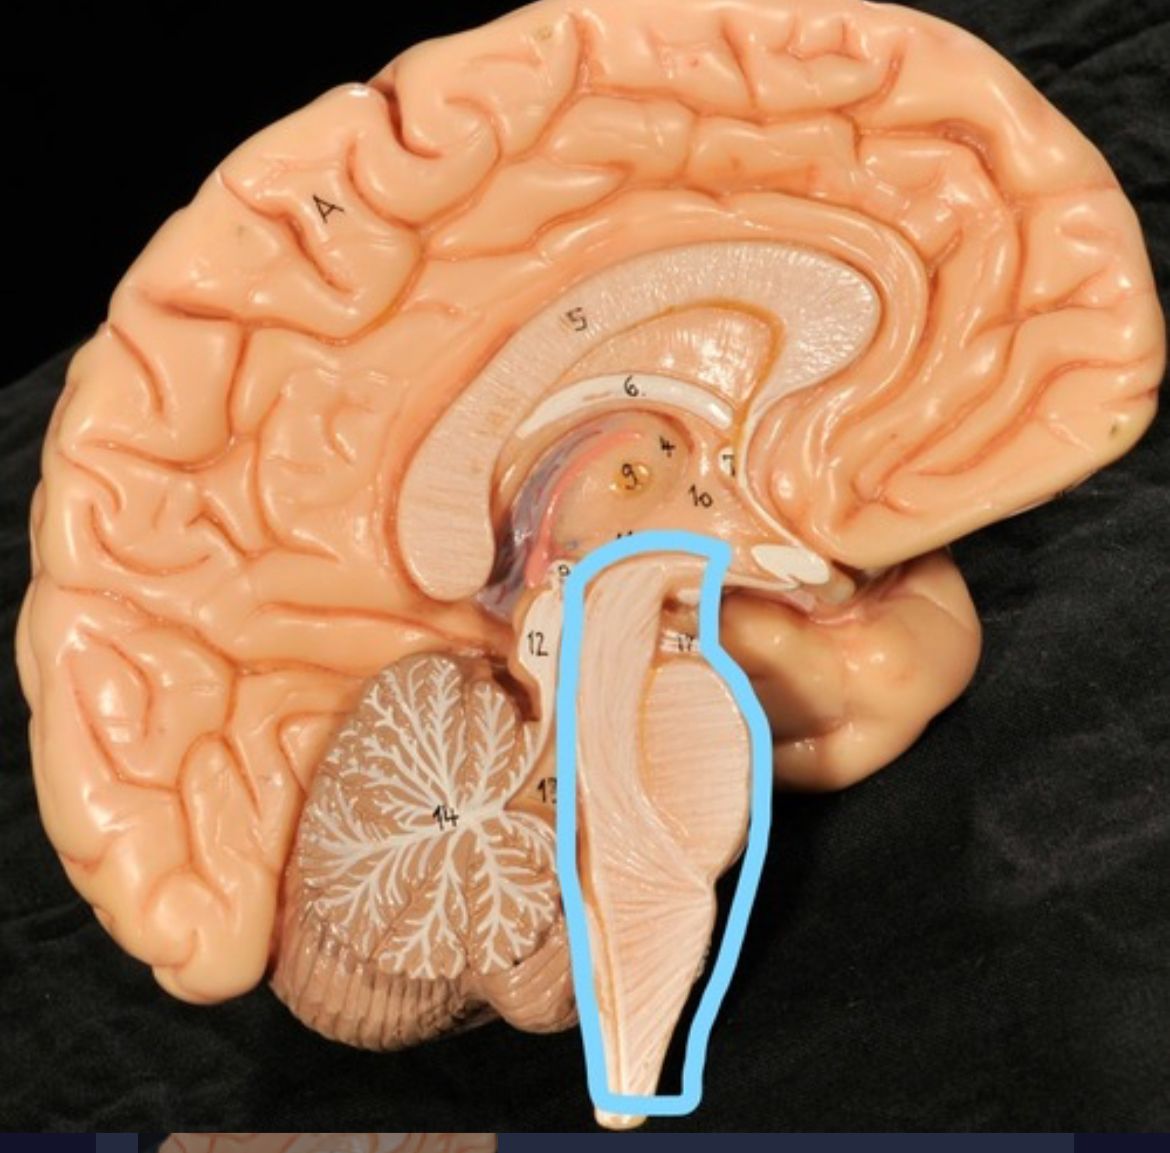

Brain stem

Pons

Medulla oblongata

Cerebral aqueduct (midrain)

4th ventricle

central canal

Spinal cord